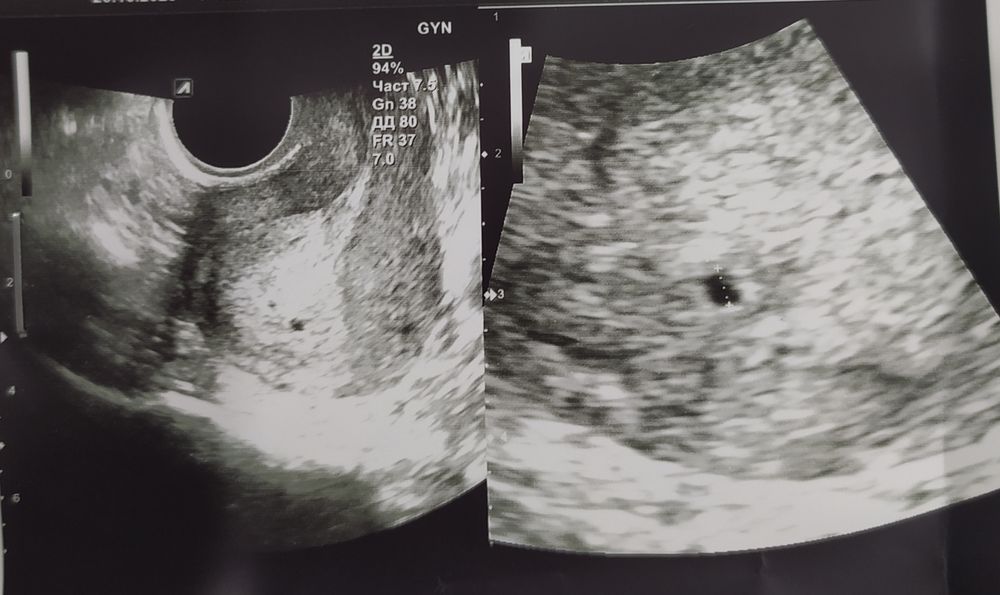

Это двойным?

Нету двойни.

Кира, автор, видимо, считает 2 точку на первом снимке 2м плодным яйцом, имея ввиду двойню 😒